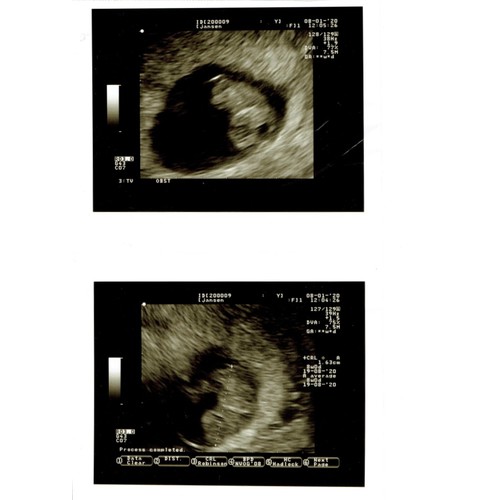

Dit is de inwendige echo met 8 weken. Met een mooi sterk hartje.

Hartje kan je niet horen met 8 weken, wel kan je het zien kloppen. En dat is net zo magische🥰